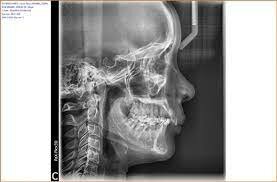

investigadores japoneses

desarrollan un sistema dental de combinación de rayos X.